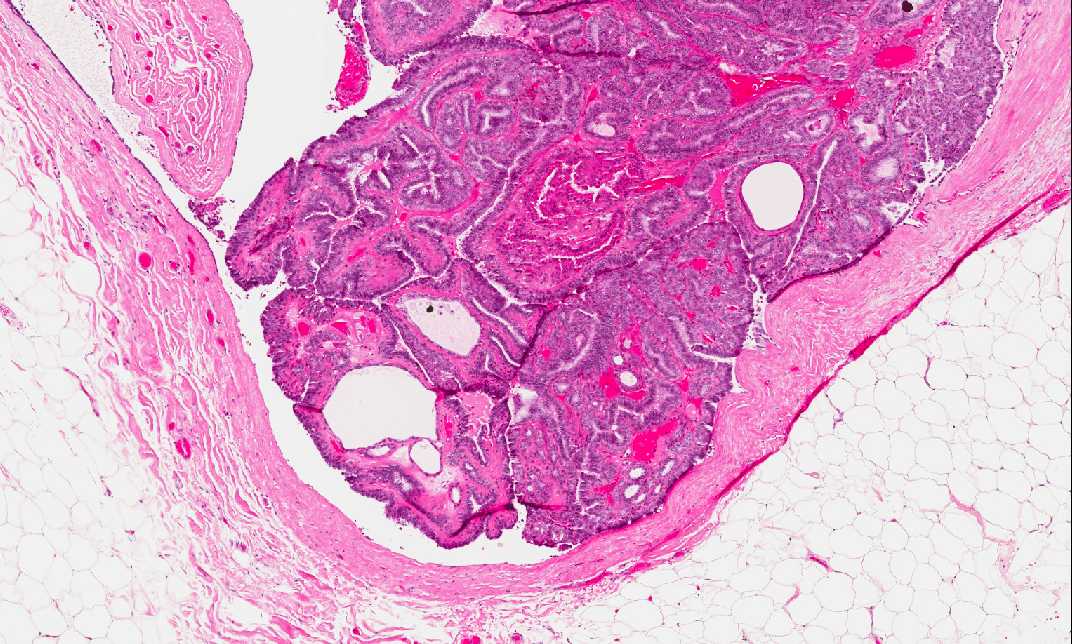

• First, there is no invasive carcinoma in this slide. The arrow point to the black ink which marks the true margin of the tumor. What is being shown here is an incidental finding.

• There is a well-circumscribed lesion embedded within a background of adipose tissue (a). The lesion seems to have a collagenous wall which represents a dilated duct (Area 1).

• There is a papillary lesion composed of a finger-like fibrovascular structure lined by a single layer of cells in most areas. Benign hyperplastic proliferation is present focally in some areas. There is no high grade pleomorphism (Area 2). The lesion has expanded the duct.

• In some areas, the lining cells are enlarged and with bright eosinophilic cytoplasm. These areas represent apocrine metaplasia (oncocytic changes) and are benign.

• The overall features are that of an intraductal papilloma and is benign.